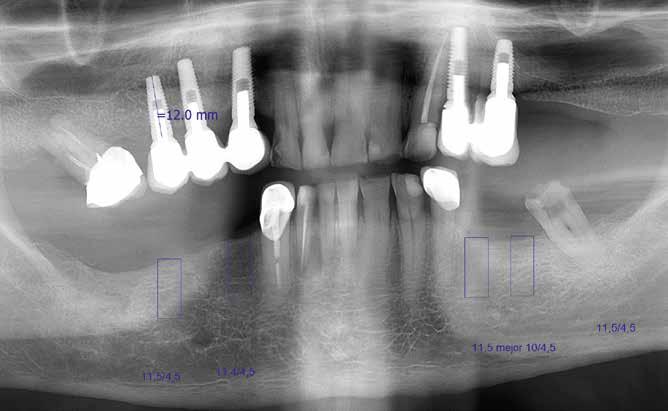

A kezelőorvos rendelőjében teljesen fogatlan maxillájú páciens jelentkezett, mind esztétikai, mind funkcionális szempontból elégtelen fogpótlással. Négy implantátumon megtámasztott fogsorról volt szó.

szükséges információ rögzítésére megfelelt. A meglévő pótlásról is készült egy ún. BioCopy-Scan (1. ábra), amelyet összevetíthetünk a felső állcsontról készült, az adhezív sapkákat is tartalmazó beolvasással (Atlantis Conus Abutment, Dentsply Sirona). Így meghatározhattuk a vesztibuláris szituációt és a vertikális helyzetet, ami megkönnyíti a funkcionális és esztétikai szempontból is kiemelkedő munka elkészítését. Ellenőriztük a meglévő pótlás egyensúlyát és érintkezési pontjait (3–4. ábrák), meghatároztuk a minta tengelyét (5. ábra), majd az adatokat az inLab szoftverbe importáltuk.